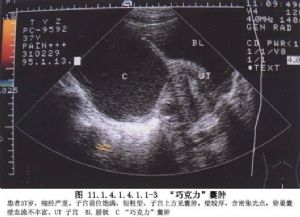

子宫内膜异位症是指:有活性的内膜细胞种植在子宫内膜以外的位置而形成的一种女性常见妇科疾病,内膜细胞本该生长在子宫腔内,但由于子宫腔通过输卵管与盆腔相通,因此使得内膜细胞可经由输卵管进入盆腔异位生长。

不孕:子宫内膜异位症患者常伴有不孕,子宫内膜异位症患者中,不孕率40%~50%。主要是因为子宫内膜异位症常可引起输卵管周围粘连影响卵母细胞捡拾,或因卵巢病变影响排卵。

子宫内膜异位症确诊的金标准是腹腔镜或者是取出来的组织送病理的病理结果。